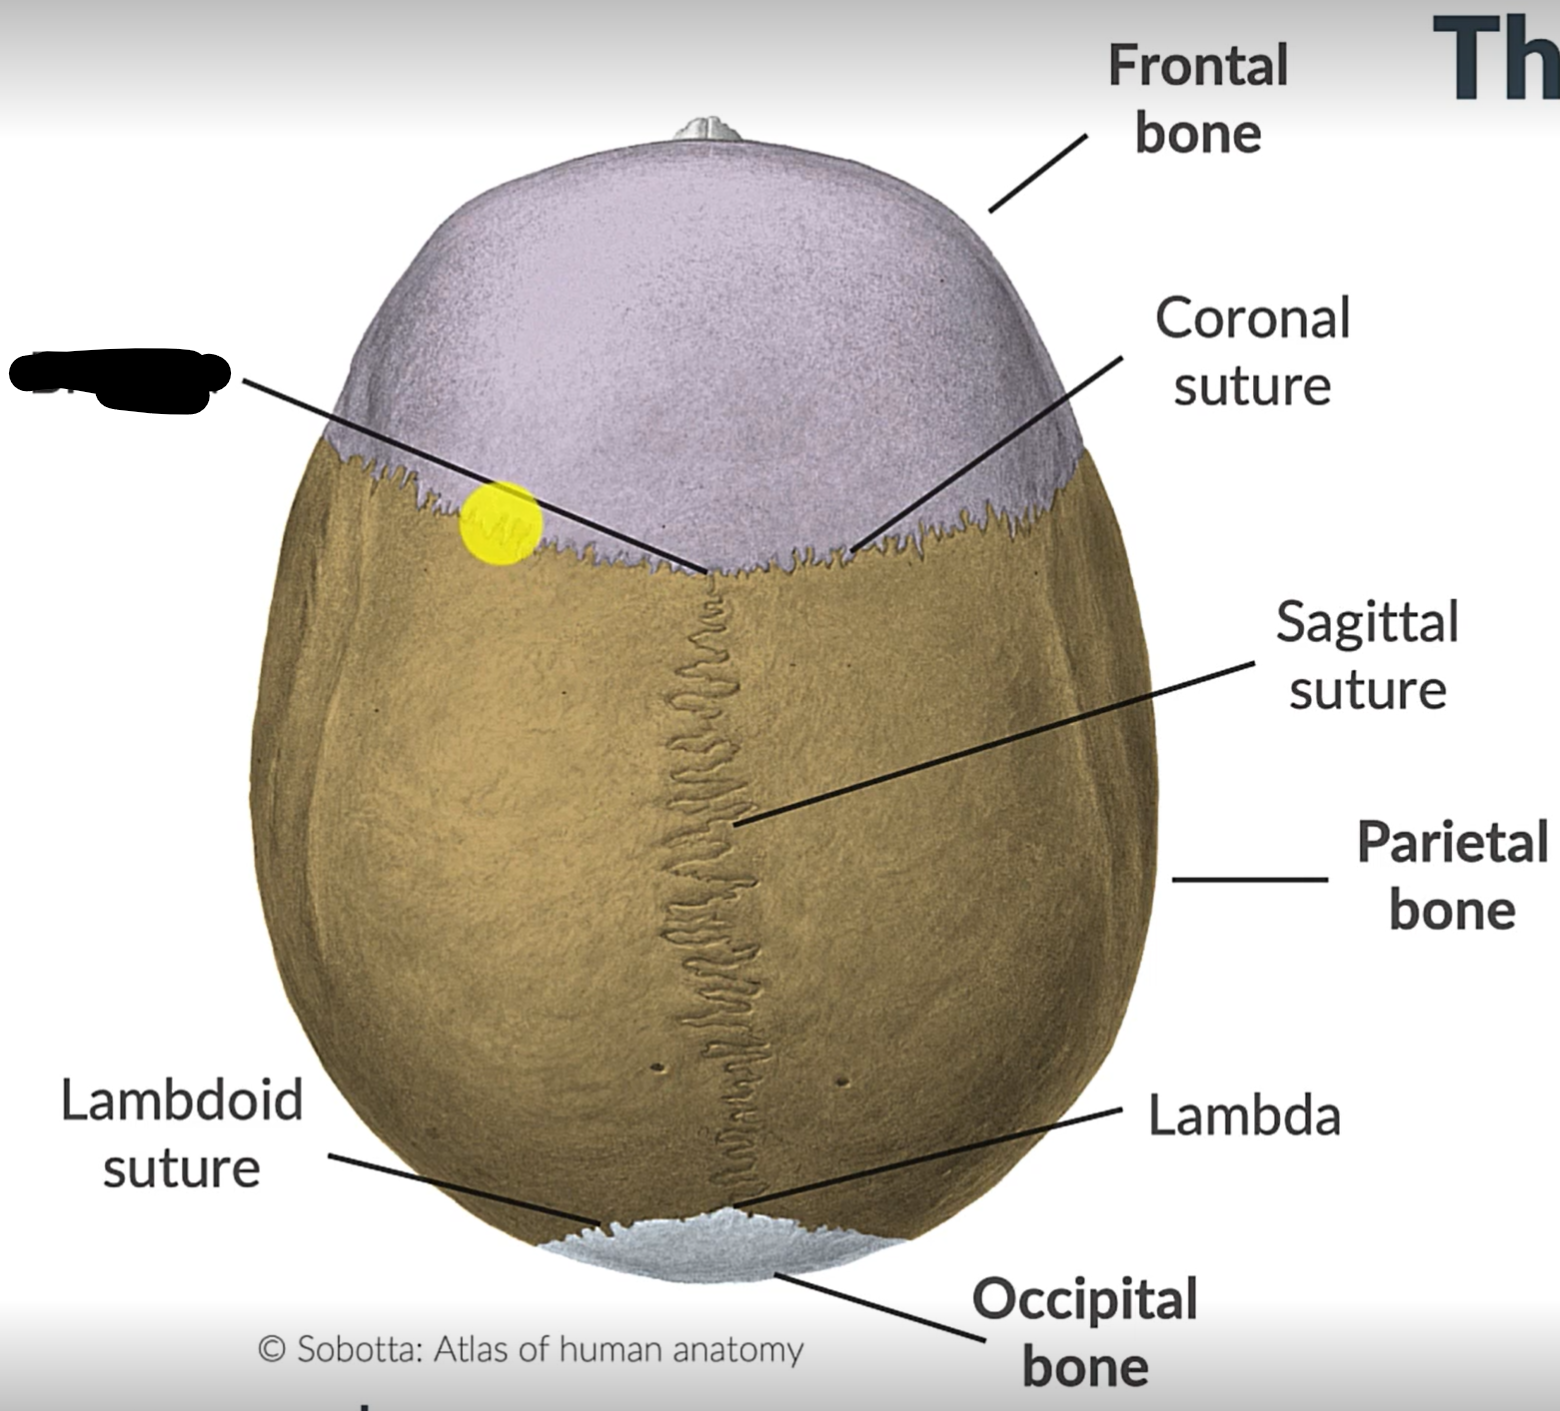

What are the 4 cranial sutures and what do they separate?

Lambdoid - separates occipital from parietal and temporal

Sagittal - extends between parietal bones

Coronal - divides frontal and parietal bones

Squamous - either side of cranium, separates temporal and parietal bones

What is the pterion?

The point where the frontal, parietal, sphenoid and temporal bones meet.

Sagittal suture

Parietal bone

Lambdoid suture

Occipital bone

What is the point where the frontal and parietal bones meet?

Bregma

Lambda